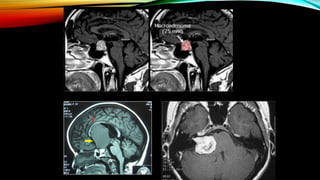

¿Qué es el condroma?

Tumor benigno de cartílago hialino,

cuando surgen en la cavidad

medular se denominan

endocondromas o en la superficie del

hueso condromas subperiosticos o

yuxtacorticales.

•Estudios especiales

- Radiografía simple de cráneo

Signos Radiológicos: Signo del anillo en C o en O.

- TAC- masa de densidad variable debido a los

diferentes grados de calcificación con mínima a

moderada captación de contraste.

- RM- masa bien circunscrita sin edema perilesional